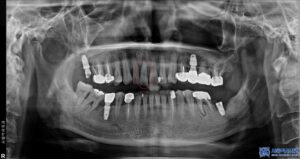

위 환자분은 위 앞니가 심하게 흔들리면서

씹을 때마다 불편감을 느낀다고 하셨는데요.

진단 결과, 문제의 치아는 위 앞니 중에서도

정중앙에 위치한 오른쪽 큰 앞니로,

치아 상태도 많이 나빠져 있었고

만성 치주염으로 인해 치근 끝에

염증이 크게 퍼져 흔들림이 있는 상태였습니다.